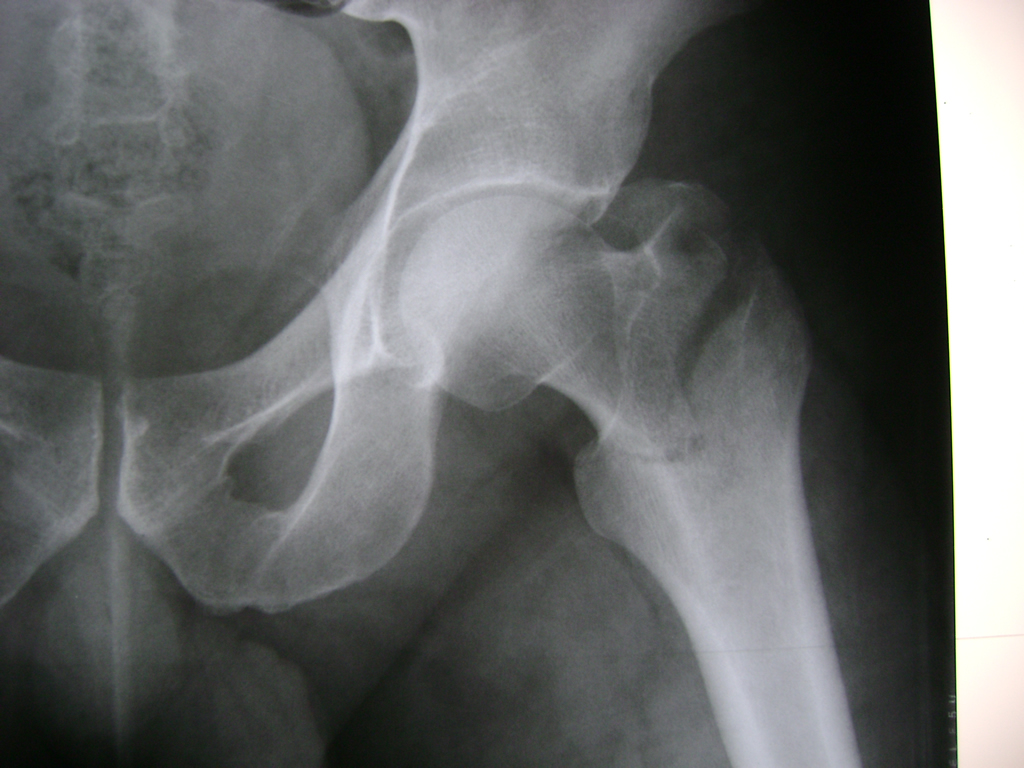

La cirugía de fractura de cadera se realiza para reparar una ruptura en la parte superior del hueso del muslo. Este hueso se denomina fémur.

Es parte de la articulación coxofemoral. Si una fractura de cadera no recibe tratamiento, es posible que deba permanecer en una silla o en la cama.